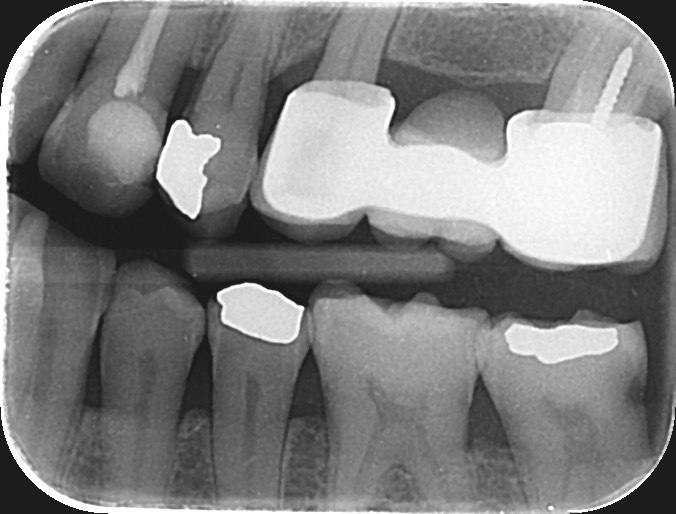

4. Which surface needs restoration?